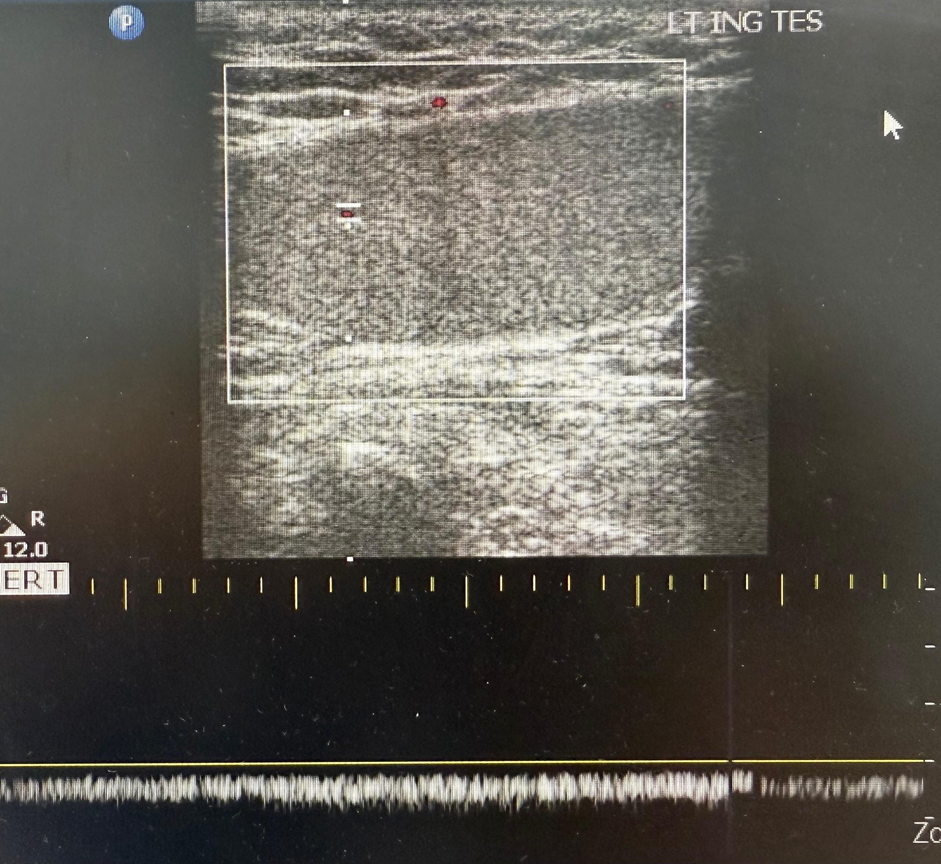

1.  Bedside Ultrasound (POCUS - Philips EPIQ 7):

- Left testis: No blood flow

- Right testis: Decreased flow, undescended position

2. Formal Doppler Ultrasound (King Salman Hospital Radiology):

- Right testis: Absent vascularity, swollen epididymis, twisted spermatic cord

- Left testis: Decreased vascularity (inguinal position)

- Mild right hydrocele

Fig 1

Figure 1